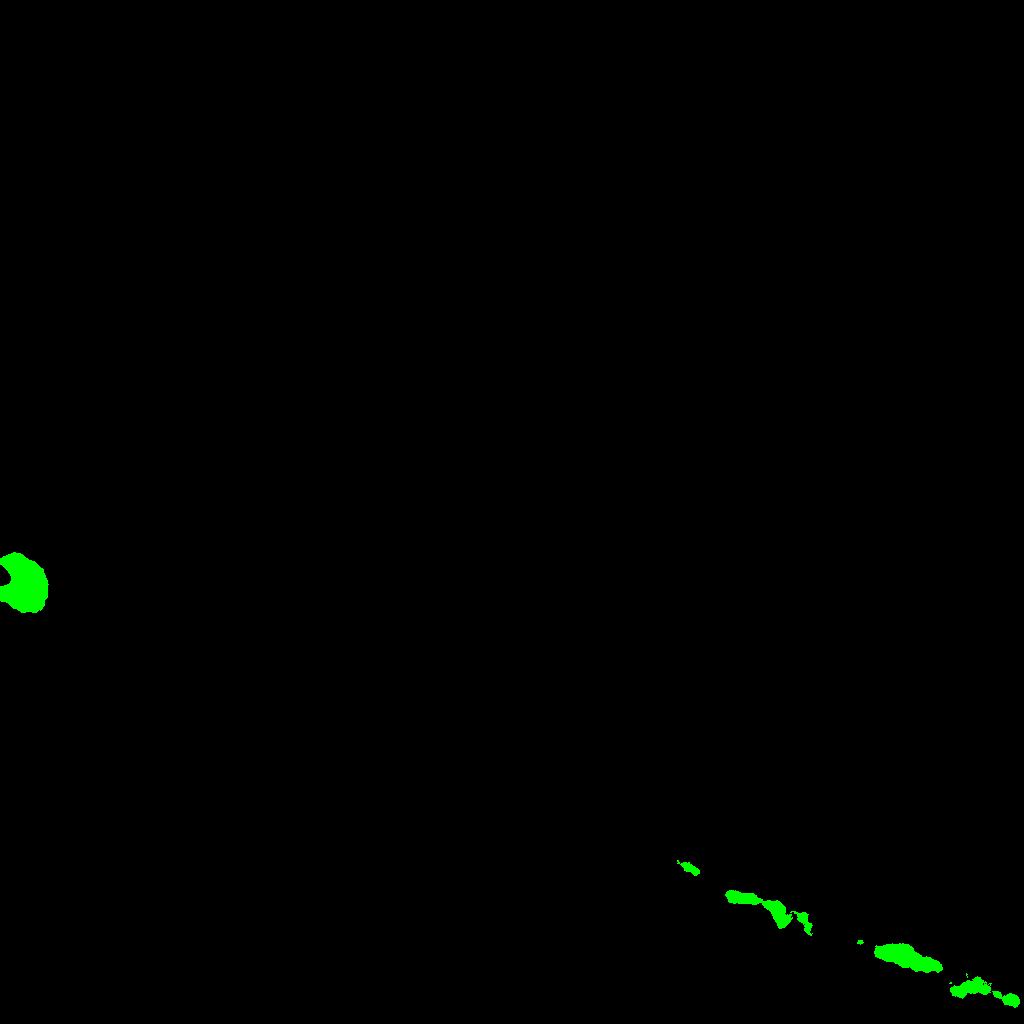

In order to construct a filtration of the binary image associated with the maximum projection image we proceed as follows. Dmsuperscript𝐷𝑚D^{m} is the maximum projection image. Dm1superscript𝐷𝑚1D^{m-1} consists of the connected components of Dmsuperscript𝐷𝑚D^{m} whose intersection with the first slide of the stack is non empty. Dm2superscript𝐷𝑚2D^{m-2} consists of the connected components of Dm1superscript𝐷𝑚1D^{m-1} whose intersection with the second slide of the stack is non empty, and so on. In general, Dmnsuperscript𝐷𝑚𝑛D^{m-n} consists of the connected components of Dmn+1superscript𝐷𝑚𝑛1D^{m-n+1} whose intersection with the n𝑛n-th slide of the stack is non empty. In this way, a filtration of the maximum projection image is obtained, see Figure 3.

Refer to caption\subseteqD0superscript𝐷0D^{0}Refer to caption\subseteqD1superscript𝐷1D^{1}Refer to caption\subseteqD2superscript𝐷2D^{2}Refer to caption\subseteqD3superscript𝐷3D^{3}Refer to caption\subseteqD4superscript𝐷4D^{4}Refer to caption\subseteqD5superscript𝐷5D^{5}Refer to caption\subseteqD6superscript𝐷6D^{6}Refer to caption\subseteqD7superscript𝐷7D^{7}Refer to captionD8superscript𝐷8D^{8}

Figure 3: A series of pictures depicting the process of filtration from the z-stack of Figure 1. From D0superscript𝐷0D^{0} to D8superscript𝐷8D^{8}: Starting on D0superscript𝐷0D^{0} and following to D8superscript𝐷8D^{8} each level of the filtration represent the containing, \subseteq information from the previous level. D8superscript𝐷8D^{8} contains all the connected components from the image.

As we know that the neuron appears in all the slides of the stack, the component D0superscript𝐷0D^{0} of our filtration will be the structure of the neuron. As a final remark, we can notice that the construction of the filtration reaches a point where it is stable; that is, a level of the filtration Disuperscript𝐷𝑖D^{i} of the filtration such that Djsuperscript𝐷𝑗D^{j} is equal to Disuperscript𝐷𝑖D^{i} for all 0j<i0𝑗𝑖0\leq j<i. An example can be seen in the components D0superscript𝐷0D^{0} to D4superscript𝐷4D^{4} of Figure 3. This observation will be important in the next subsection.